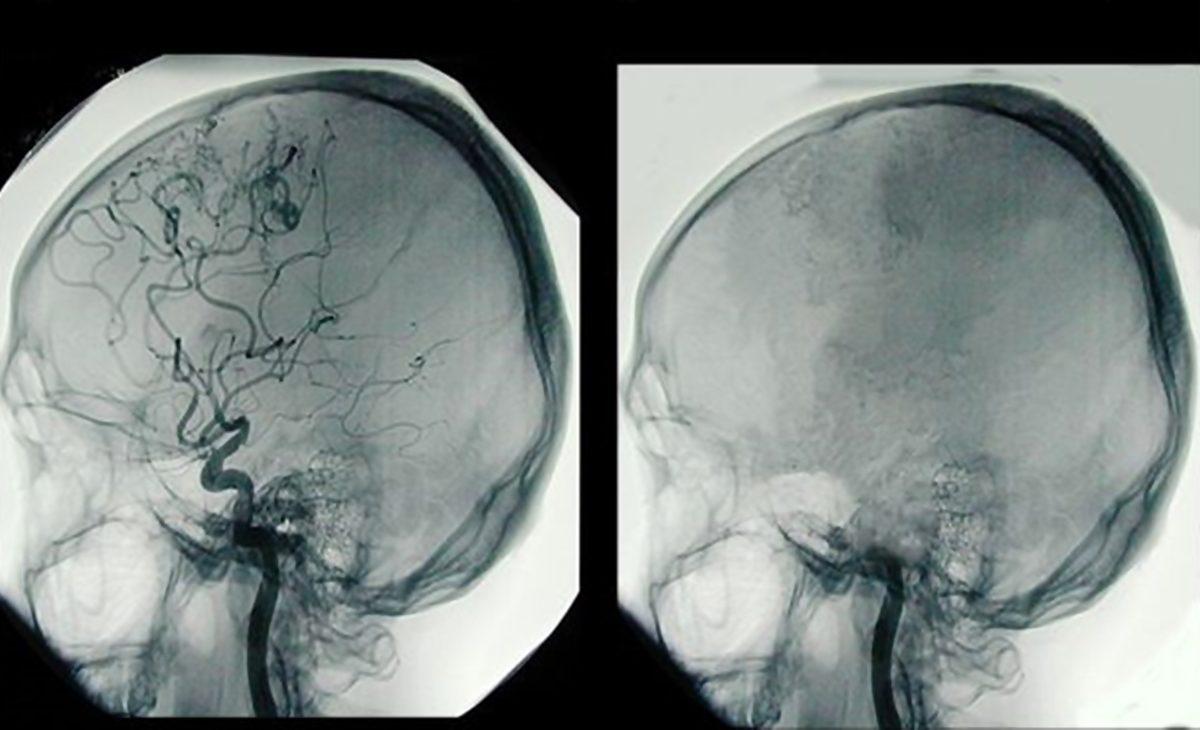

- Koma/bitkisel hayat ve beyin ölümü karşılaştırması

Serebral anjiografi tekniğiyle yapılan bir görüntüleme. Bu teknikte sadece beyin damarları görüntülenir.

- Sintigrafi yöntemiyle görüntülenen beyin ölümü.

Sintigrafi, radyoaktif bir maddenin vücuda; damar, ağız veya diğer yollarla verildikten sonra özel kameralar ile vücudun görüntülendiği tanı yöntemidir.